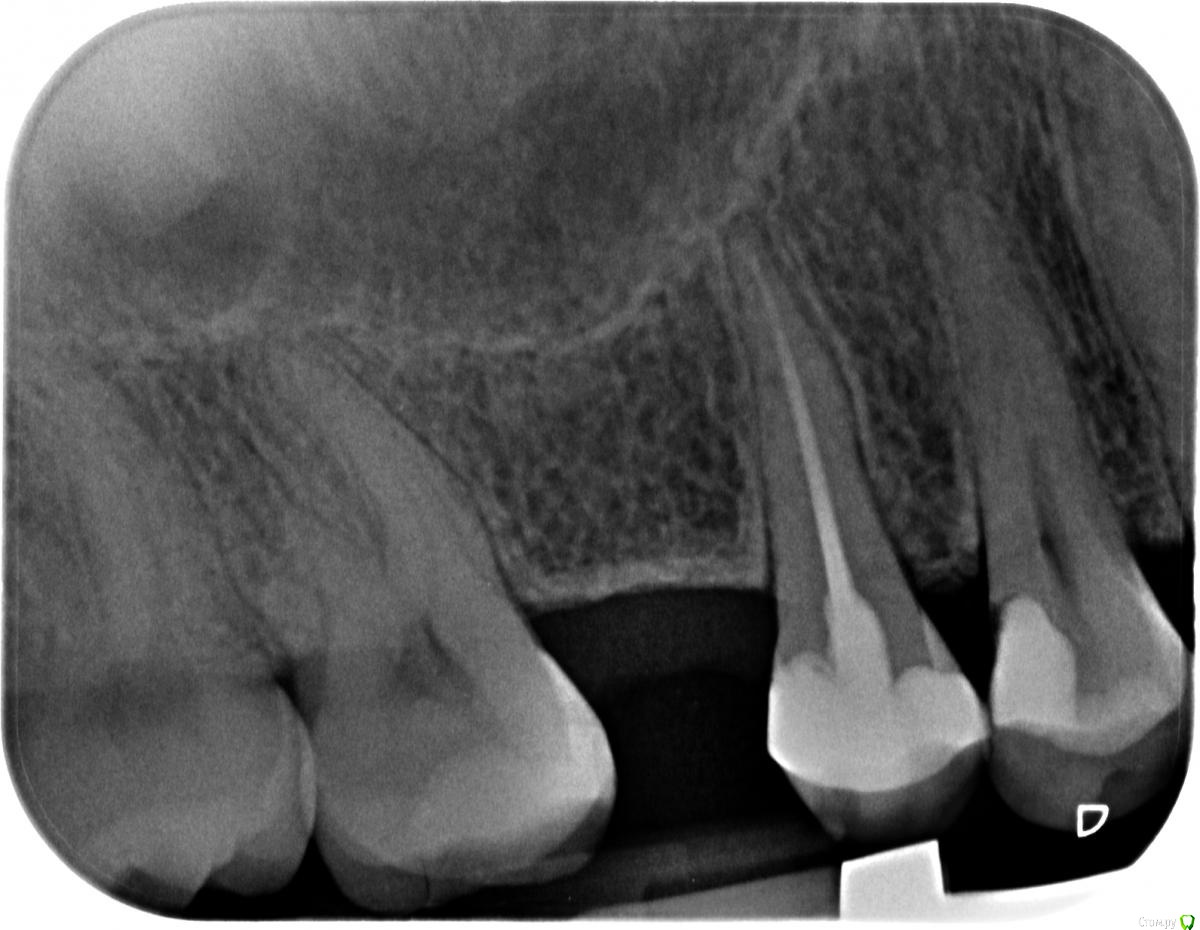

pin-up Опубликовано 21 мая, 2017 Поделиться Опубликовано 21 мая, 2017 (изменено) Здравствуйте!С зубами мне не везет. Врач три года назад сделал пломбу ( 4-ка), стала замечать что зуб ноет время от времени. Сделала рентген, мой стоматолог сказал, что нужно перелечивать и нерв уже не спасти. Это меня очень расстроило, так как мне 28 лет, а зубы уже латаные перелатаные и два отсутствуют. Поэтому хочу спросить мнение других специалистов, есть ли у меня хоть какой -то шанс спасти нерв зуба? Изменено 21 мая, 2017 пользователем pin-up Ссылка на комментарий

Zlata-doctor Опубликовано 22 мая, 2017 Поделиться Опубликовано 22 мая, 2017 Я бы не была столь категорична. Клинически обследовать 4. Разобраться с 5-может быть он беспокоит. Удалить эту дефектную пломбу на 4. Тогда в совокупности окончательно и решить. Но вы должны понимать, что вероятность эндодонтического лечения очень высока. Ссылка на комментарий

DmitrySH Опубликовано 22 мая, 2017 Поделиться Опубликовано 22 мая, 2017 Да, пломбу на 4-том зубе точно надо переделывать. И разбираться какой беспокоит. В 5-том тоже не все благополучно на снимке Ссылка на комментарий

pin-up Опубликовано 25 мая, 2017 Автор Поделиться Опубликовано 25 мая, 2017 Скажите, а вокруг пломбы на четвертом зубе есть затемнение, это кариес? Ссылка на комментарий

DmitrySH Опубликовано 25 мая, 2017 Поделиться Опубликовано 25 мая, 2017 Скажите, а вокруг пломбы на четвертом зубе есть затемнение, это кариес? Возможно.На границе под десной точно разрушается Ссылка на комментарий